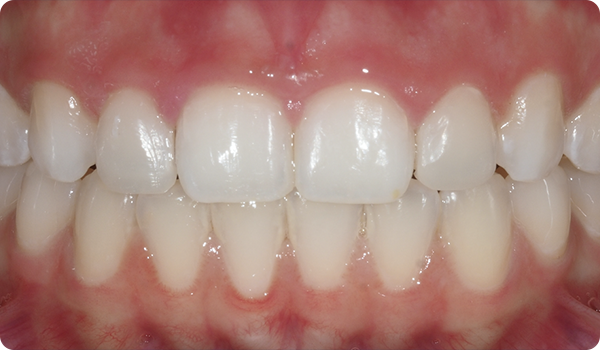

Med små rörelser korrigeras positioner och förbereder den mest lämpliga och konservativa estetiska behandlingen för dina patienter.

Leenden på plats

Med Right får dina patienter det leende de önskar, inom den tid de vill, på ett bekvämt och ”osynligt” sätt.

Att justera tänder med Right är den perfekta och mest konservativa grunden för framtida blekning eller facettbehandlingar som kommer att föra patientens leende till perfektion.